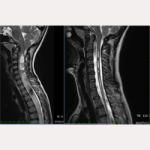

07/06/2013 Pre-SFT

30/07/2019 Post-SFT

Привет, я мама девочки, которую прооперировали в восемь лет по рассечению концевой нити в декабре 2013 года. Она стала четвертой пациенткой из Японии в Барселонском Институте Киари. Моя дочь страдает мальформацией Арнольда Киари I, идиопатическими сирингомиелией и сколиозом. С момента операции прошло уже шесть с половиной лет, и все идет очень хорошо. У нее была очень большая сирингомиелическая киста до поясничного отдела, но уже через шесть месяцев после операции она уменьшилась наполовину, а через 18 месяцев осталась только третья часть того, что было. Киста еще есть, но она понемногу уменьшается. Через два с половиной года появились первые изменения в положении миндалин мозжечка, а через четыре с половиной года произошло еще больше улучшений. Врач моей дочери в Японии был удивлен таким результатом рассечения концевой нити и сказал, что раз киста так сильно уменьшилась, то она не будет давать новых проблем. Однако, так как полностью остановить сколиоз уже было нельзя, Институт порекомендовал нам метод Шрот и через 4 месяца после операции моя дочь начала по нему заниматься. На четыре года мы смогли остановить развитие искривления, но когда дочка вступила в подростковый период, в декабре 2018 года, ее сколиоз ухудшился до 48 градусов, поэтому мы решили поменять центр реабилитации, и уже через месяц она улучшила результат до 33 градусов, и мы продолжаем занятия, чтобы снизить сколиоз.

07/06/2013 Pre-SFT

07/06/2013 Pre-SFT 30/07/2019 Post-SFT

30/07/2019 Post-SFT The Filum disease and the Neuro-Cranio-Vertebral Syndrome: definition, clinical picture and imaging features.

The Filum disease and the Neuro-Cranio-Vertebral Syndrome: definition, clinical picture and imaging features.